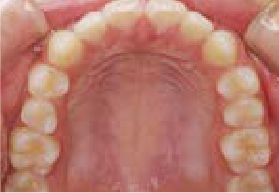

Jさん (矯正開始時:8歳)

Before

After

歯がガタガタに並んでいて、前歯の真ん中の位置が少し左にずれていました。

奥歯が生えるためのスペースが足りず、永久歯が生えて来られない状況が確認できました。

また、飲み込むとき下くちびるに力が入ってしまうクセが見られ、お顔全体の成長が遅れている様子が確認できました。

治療を終えて

歯がきれいに生えるためのスペースをしっかり確保することができ、歯並びを乱していたお口のクセも改善されたため、奥歯が生えるスペースを確保することができました。

しっかり噛めるかみ合わせを作ることが、将来の健康につながるので「よく噛む」練習も続けてもらっています。

主訴・治療内容 歯がガタガタになってきたことに悩み、無料相談に来院されました。

治療期間 3年

費用 462,000円(税込)